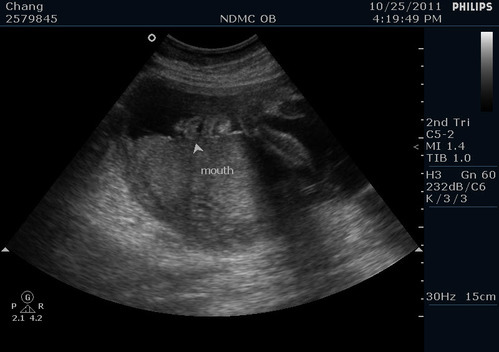

寶貝的豐唇!醫生說沒有兔唇喔! 寶貝全程都嘴開開睡覺啦~

而且醫生很可愛~還先看看我跟我老公後說小寶貝應該會像我比較多(因為我的嘴唇比我老公厚)